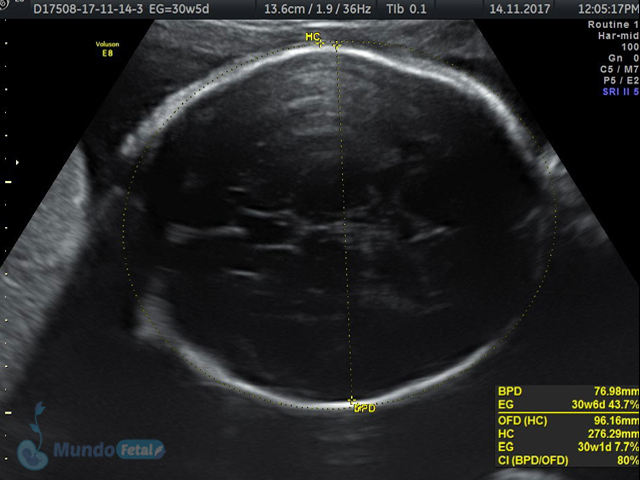

Se recomienda de 32-34 semanas, realizando valoración de crecimiento armónico (4 medidas específicas), valoración anatómica, líquido amniótico, flujos sanguíneos fetales y placentarios perfilando el bienestar fetal hacia el final de embarazo.